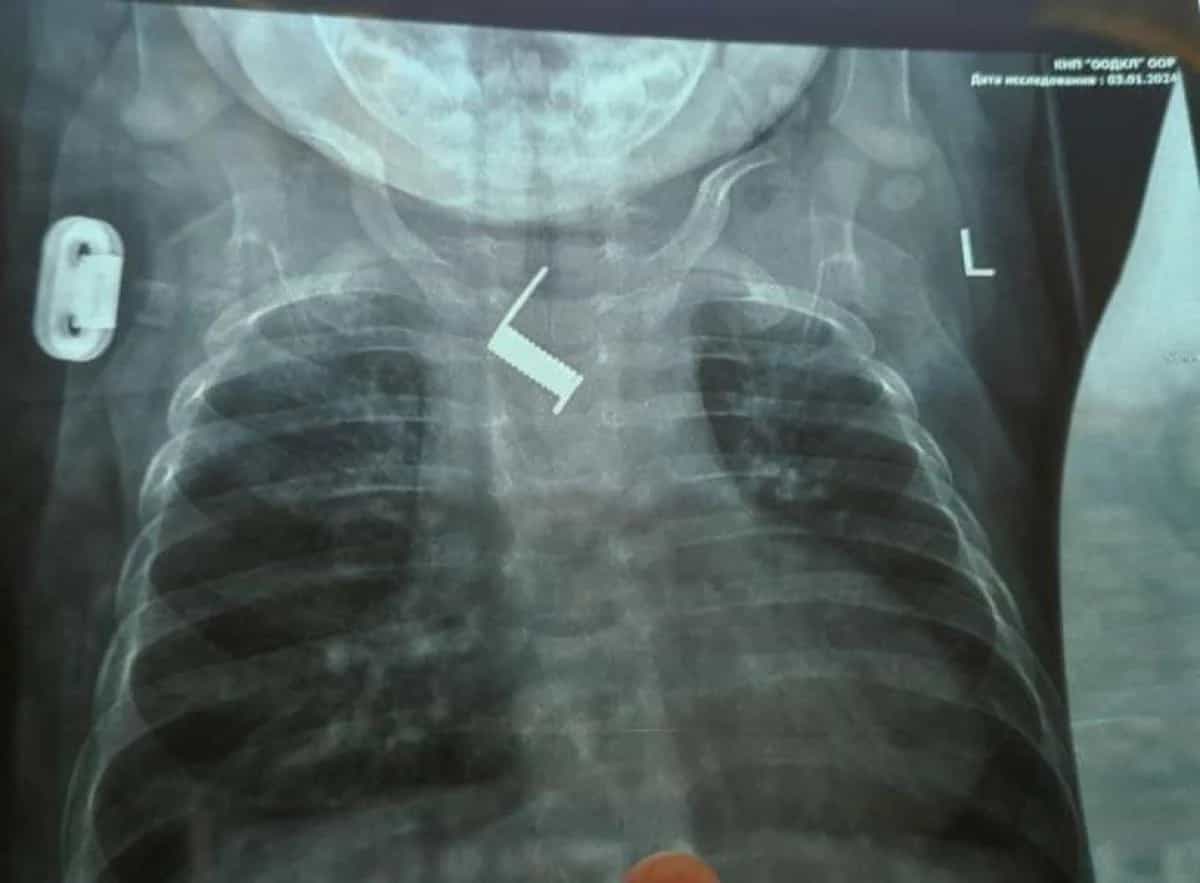

В Одесі врятували малюка з пружиною у стравоході: до того крихітку два тижні "лікували" від бронхіту